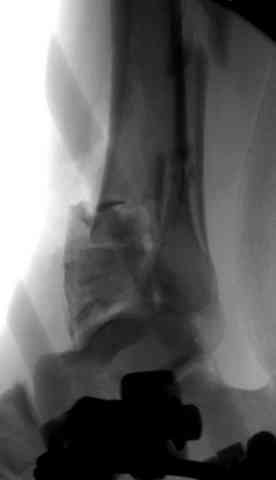

Здесь выставлена пара случаев перелома пилона, оба

случая леченные этапным наружным фиксатором.

Второй случай фиксирован аппаратом Илизарова.